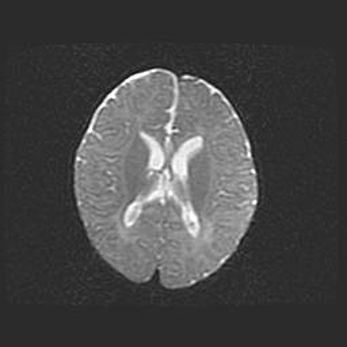

Церебральная ишемия II.

Возраст: 7 дней

Вес: 3350 г

Пол: женский

Окружность головы: 35 см

Срок гестации: 39 недель

Ишемия головного мозга – это состояние, которое развивается в ответ на кислородное голодание вследствие недостаточного мозгового кровообращения. У новорожденных она является следствием дефицита кислорода, что ведет к метаболическим расстройствам различной степени тяжести в тканях головного мозга, в том числе к развитию коагуляционных некрозов и гибели нейронов.